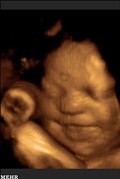

براستی چه چیز باعث می شود این حالت ها بر صورت جنین نقش ببندد ؟

به آیه های زیر دقت کنید:

و هم اوست که میخنداند و میگریاند (۴۳)

وَأَنَّهُ هُوَ أَضْحَکَ وَأَبْکَى ﴿۴۳﴾

و هم اوست که میمیراند و زنده میگرداند (۴۴)

وَأَنَّهُ هُوَ أَمَاتَ وَأَحْیَا ﴿۴۴﴾

و هم اوست که دو نوع میآفریند نر و ماده (۴۵)

وَأَنَّهُ خَلَقَ الزَّوْجَیْنِ الذَّکَرَ وَالْأُنثَى ﴿۴۵﴾

از نطفه‏اى چون فرو ریخته شود (۴۶)

مِن نُّطْفَةٍ إِذَا تُمْنَى ﴿۴۶﴾